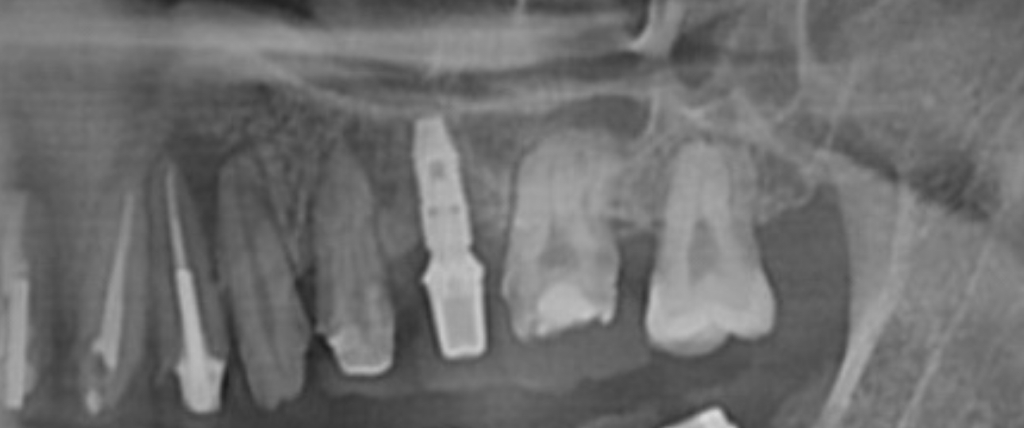

Ct로 임플란트 투바디인지 원바디인지 알 수 있을까요?

혹시 이 사진을 보고 일체형인지 투바디인지 알 수 있을까요?

( 지대주 제거가 가능한건지)

아니면 씨티로는 모르고 직접 열어봐야 알 수 있나요?

존경하는 의사선생님 이게 원바디인지 투바디인지 알 수 있다면 답변해 주시면 감사하겠습니다

• 1번 째 사진

• 안녕하세요. 김철진 치과의사입니다.

임플란트에 어벗트 먼트가 올라간게 투바디로 임플란트를 진행한거 같습니다. 안쪽에 나사를 풀면 지대주는 제거 가능합니다.